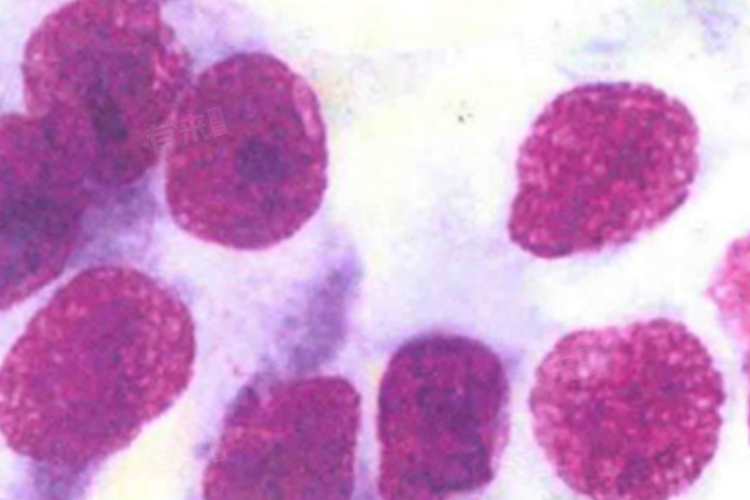

- 肿瘤特性:dMMR的肿瘤通常具有较高的突变负荷,这些突变可以产生新的抗原,增加肿瘤被免疫系统识别的可能性。

- 治疗反应:dMMR的肿瘤对免疫治疗的反应往往较好,因为免疫治疗药物能够利用肿瘤产生的新抗原,激活机体的免疫反应来杀伤肿瘤细胞。